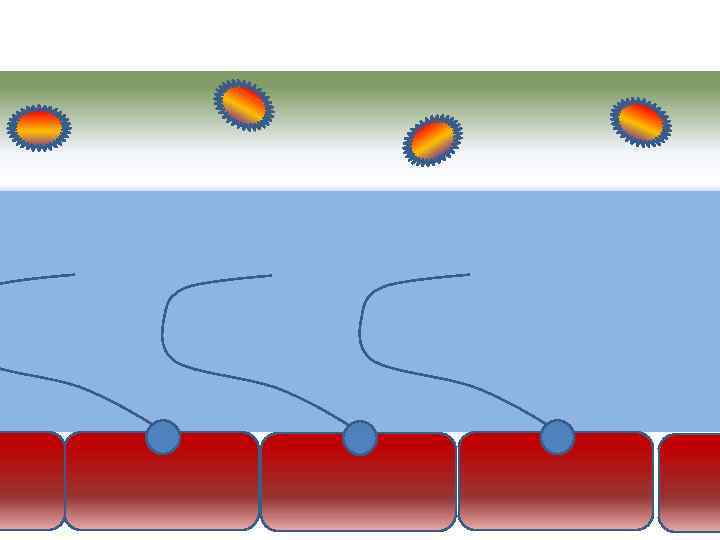

Факторы риска Недостаточное увлажнение дыхательной смеси Высушивание трахеи и бронхов

Факторы риска Недостаточное увлажнение дыхательной смеси Высушивание трахеи и бронхов

Факторы риска Недостаточное увлажнение дыхательной смеси ! Слизистая оболочка трахеи и бронхов обязательно должна быть укрыта секретом

Факторы риска Недостаточное увлажнение дыхательной смеси ! Слизистая оболочка трахеи и бронхов обязательно должна быть укрыта секретом

Факторы риска Недостаточное увлажнение дыхательной смеси • естественное удаление бактерий • состояние эпителия трахеи и бронхов

Факторы риска Недостаточное увлажнение дыхательной смеси • естественное удаление бактерий • состояние эпителия трахеи и бронхов

Оптимальное увлажнение 37°С, 44 мг/л Оптимальная влажность • Уменьшает время нахождения патогенной флоры в легком

Оптимальное увлажнение 37°С, 44 мг/л Оптимальная влажность • Уменьшает время нахождения патогенной флоры в легком

Оптимальное увлажнение Достаточная продукция слизи Хороший транспорт Экономит энергию и воду Защитная функция

Оптимальное увлажнение Достаточная продукция слизи Хороший транспорт Экономит энергию и воду Защитная функция

Механизм защиты легкого Слизь (зеленый цвет) нейтрализует и связывает патогенную флору(синий цвет) Слизь – это барьер между клетками и патогенной флорой Слизь – это транспортное средство

Механизм защиты легкого Слизь (зеленый цвет) нейтрализует и связывает патогенную флору(синий цвет) Слизь – это барьер между клетками и патогенной флорой Слизь – это транспортное средство